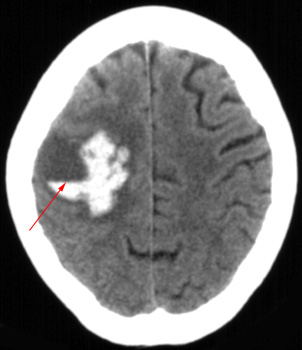

Head CT > Stroke > Coagulopathy IH

Coagulopathy related intracerebral hemorrhage can be due to drugs such as coumadin or a systemic abnormality such as thrombocytopenia. On imaging, this hemorrhage often has a heterogeneous appearance due to incompletely clotted blood. A fluid level within a hematoma suggest coagulopathy as an underlying mechanism.